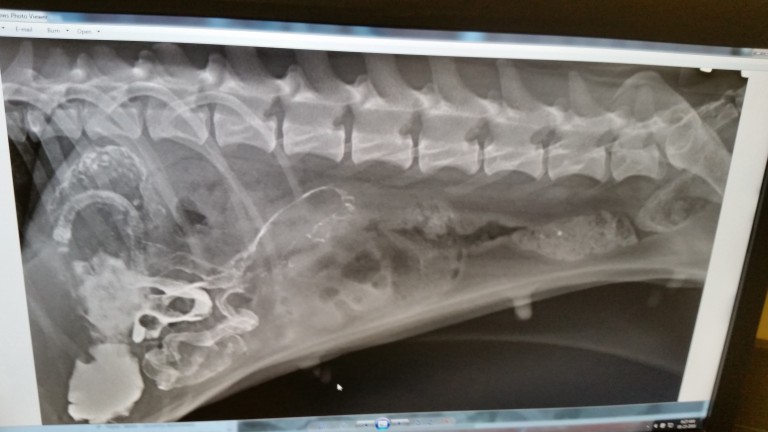

“X-rays didn’t show us what we wanted to see. She had a major blockage. Hence the throwing up. Her little body was rejecting everything. The vet gave her a warm water enema while we waiting in the room. Thirty minutes pass and the doctor returns only to tell us that she didn’t pass anything and that surgery would be needed. He gives us the estimate and we nearly throw up just as our newly found pup has done. Since we didn’t know what the blockage was, the doctor couldn’t give us a chance of survival on the surgery. He said since they were going in blind, they wouldn’t know until they actually got in there. What do we do? How do we decide if it’s worth it?”

“Her empty crate in the apartment weighed down our hearts, but we knew that the surgeons would take good care of her. We got a call midday today and the surgery was a success! The had to cut into her intestine in five different places to remove all of the cloth and plastic that she had eaten just trying to survive out on her own. She is in recovery now and they said we might be able to have her back home on Thursday. We can’t wait to have her with us again. My girlfriend has already told me that the pup will be spoiled rotten. Little One has apparently already claimed my spot on the bed, as well. Oh well, totally worth it.”